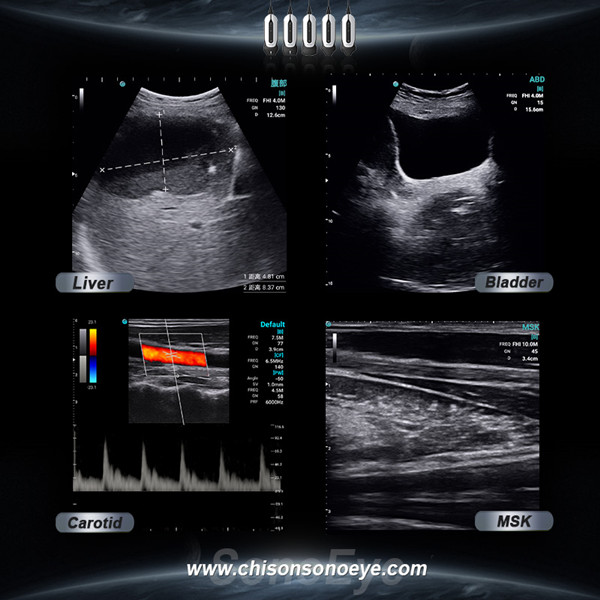

Increased Availability

Handheld ultrasound devices are typically more affordable and easier to use than traditional ultrasound machines. This increased accessibility means more healthcare providers can use them, leading to more timely and widespread diagnostic capabilities. Patients benefit from reduced wait times and more frequent access to necessary imaging.

Products: Vascular Ultrasound Machine MSK Ultrasound Machine Portable Ultrasound Device Portable Ultrasound Machine for Sale Portable Ultrasound Machine For Pregnancy Handheld Ultrasound For Pregnancy Handheld Veterinary Ultrasound Veterinary Ultrasound Machine Portable Vascular Ultrasound Livestock Ultrasound Machine